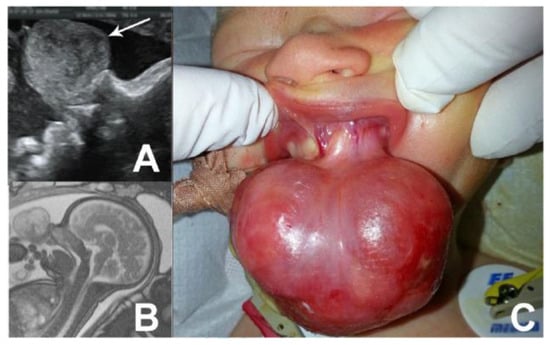

Case no. 1

Case no. 2.